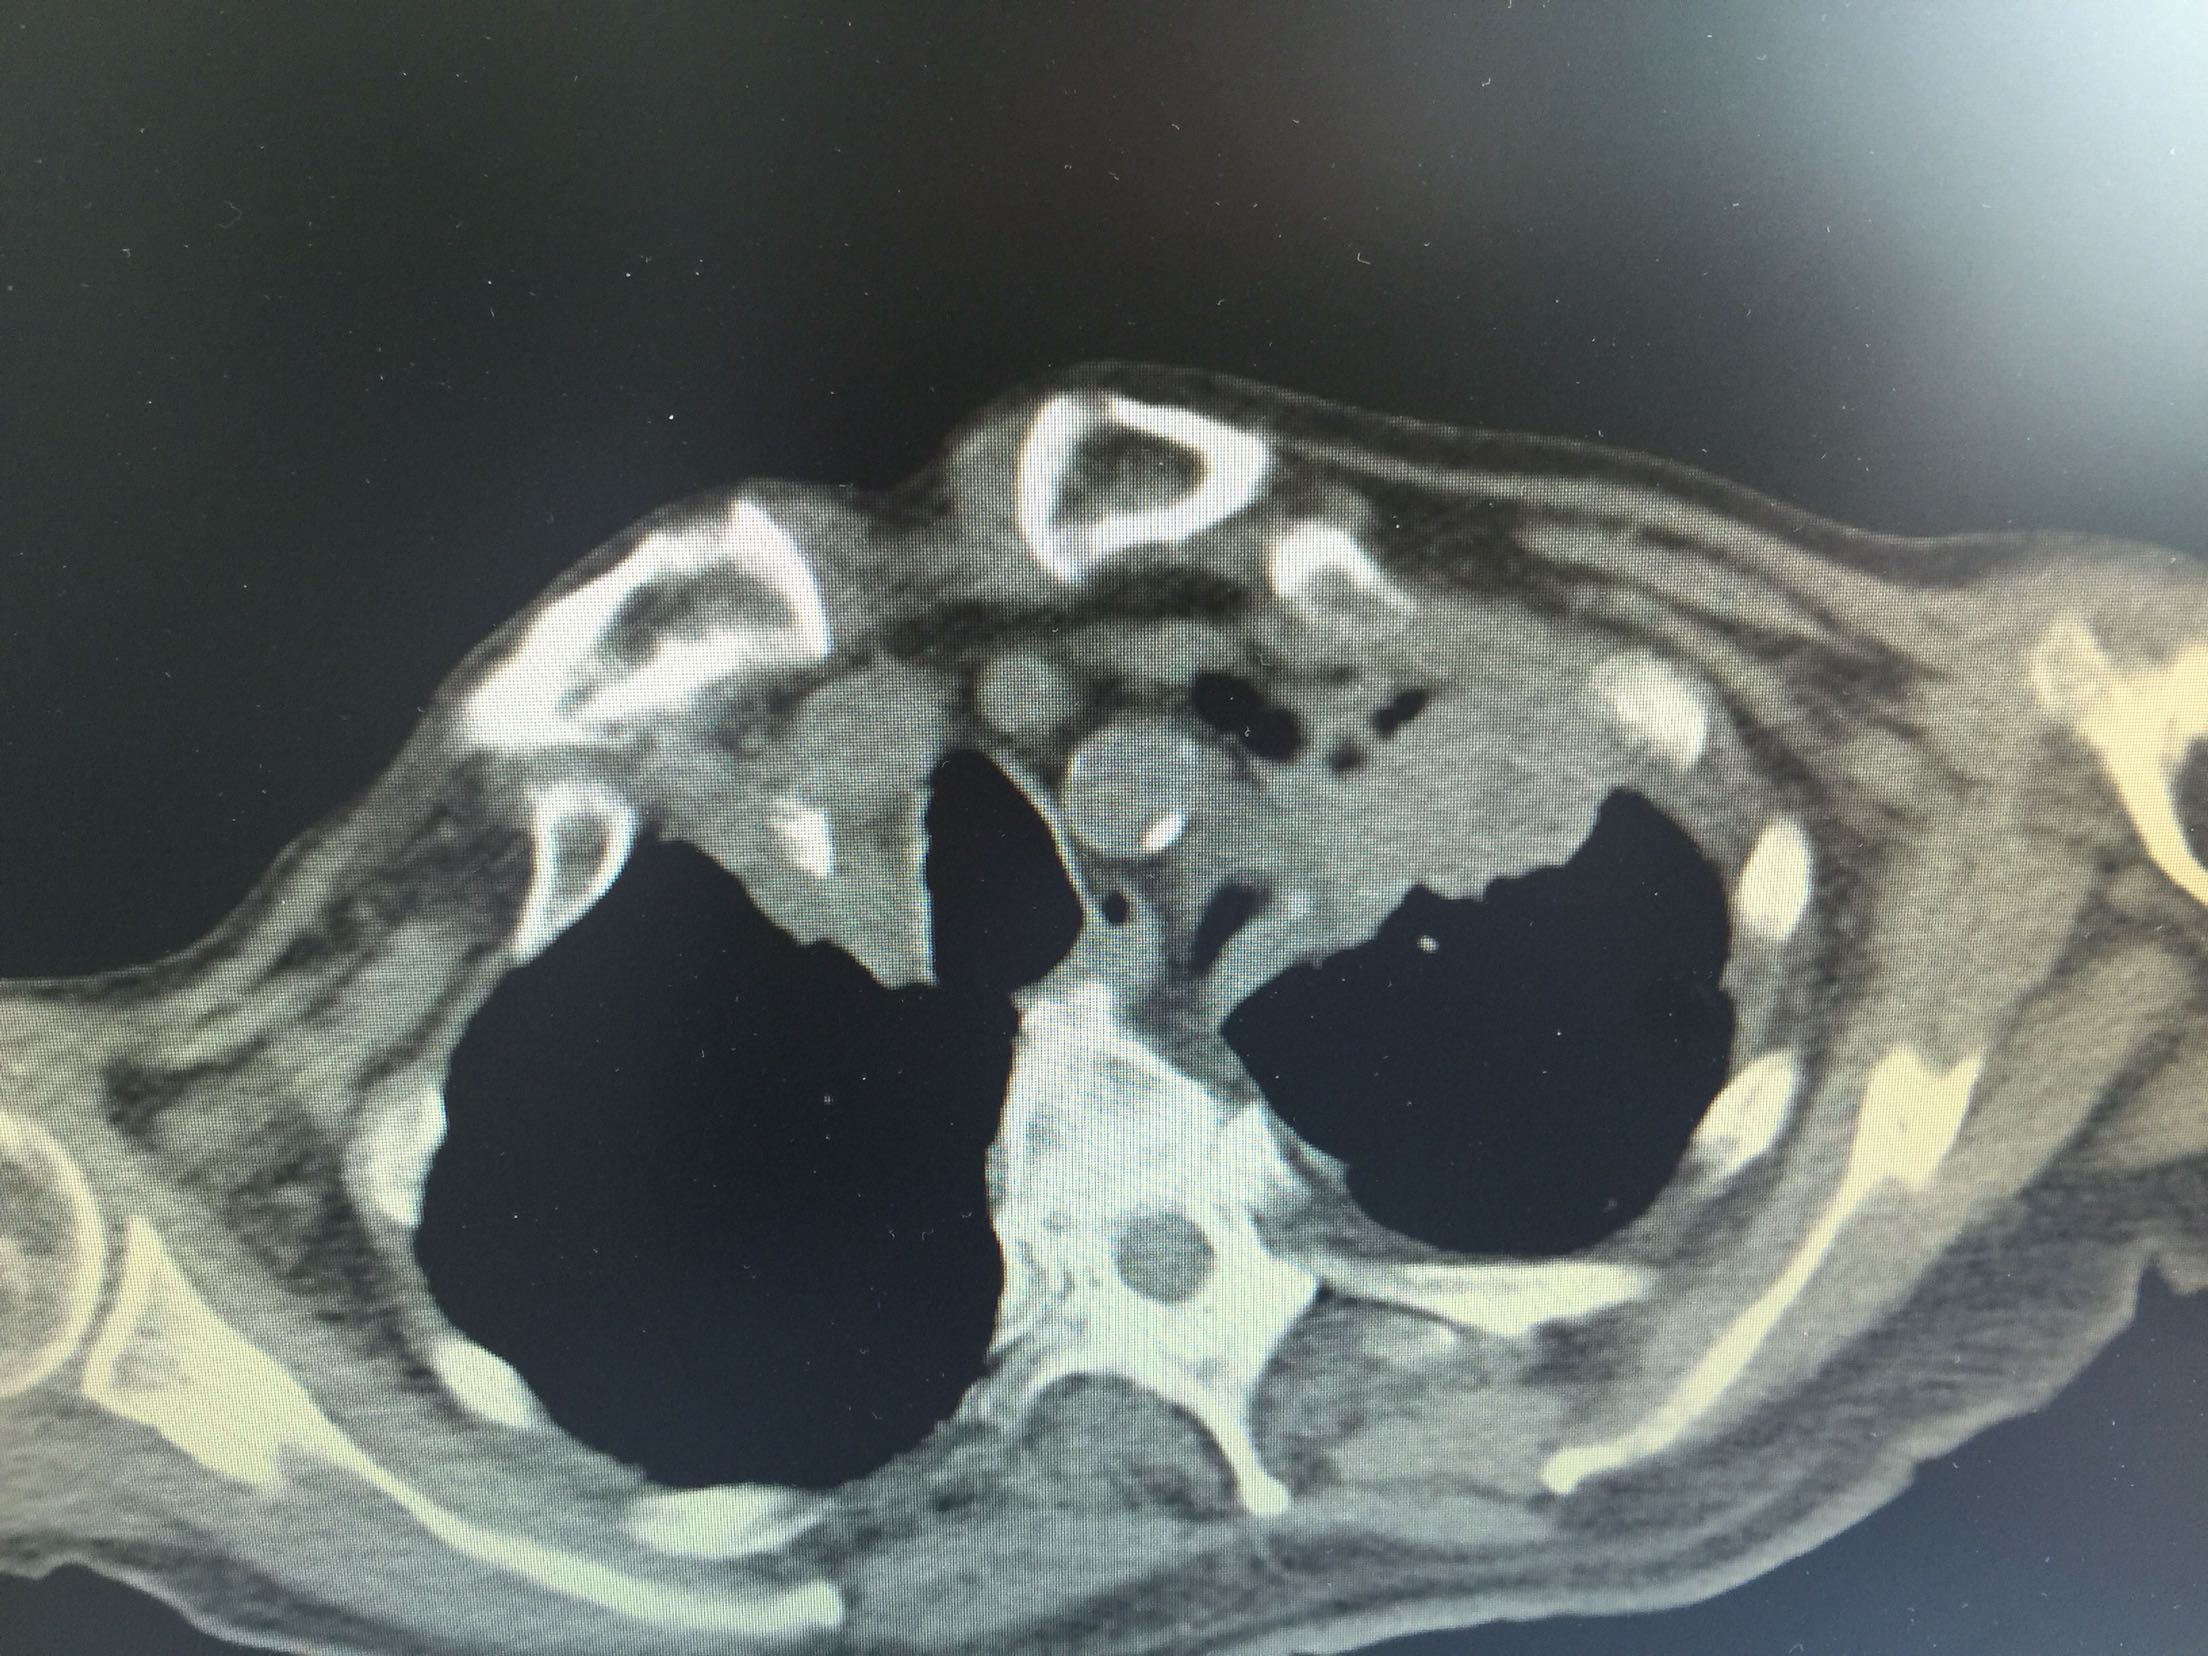

肺癌脑转移1例。

女,81岁,以“意识障碍1天”入院。

查体:浅昏迷,双眼向左侧凝视,双瞳孔等大正圆,直径3.0mm,对光反射灵敏,四肢不自主运动,肌张力正常,腱反射卄,Babinski征R-L-,脑膜刺激征阴性。

1.肺癌脑转移。 治疗:营养神经、脱水、抗感染、化痰、维持离子平衡治疗。